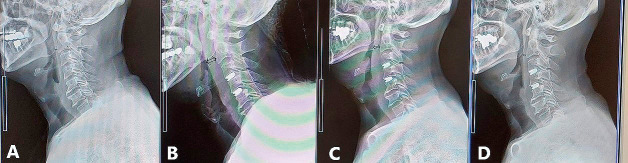

Gelatin-based hemostatic agents are widely used in neurosurgery. This is a case of postoperative aphagia strongly suspected to be caused by an allergic reaction to a gelatin-based hemostatic agent after anterior cervical decompression and fusion for central cervical cord injury. A 55-year-old man underwent cervical anterior decompression and fusion at the C3/4 and 4/5 levels for central cervical cord injury. Immediately after the surgery, he could not swallow saliva at all, but his voice was not hoarse. Postoperative cervical computed tomography and magnetic resonance imaging showed significant edema from the post-hypopharynx wall to the front of the vertebral body. The retropharyngeal space was remarkably enlarged to 15.8 mm with cervical spine X-rays. Without neurological symptom improvement, his condition was diagnosed as marked edema of the area where Surgiflo (porcine-derived gelatin-based hemostatic agent; Johnson & Johnson Wound Management, Somerville, NJ, USA) had been applied during the operation. It was strongly suspected to be caused by an allergic response to the porcine-derived gelatin. When methylprednisolone 1000 mg was administered for 3 days from the 5th postoperative day, swallowing became almost normal within a few hours after the initial administration, and his neurological symptoms improved. The patient left the hospital on the 12th day after the operation. Before using porcine-derived gelatin products during surgery, special consideration should be given to patients with an allergy history before surgery.

明胶类止血剂广泛应用于神经外科。这是一例术后失语症,强烈怀疑是由于前路颈椎减压融合治疗中心性颈髓损伤后对明胶止血剂的过敏反应引起的。55岁男性因中心性颈髓损伤行颈椎前路减压和C3/4和4/5节段融合术。手术后,他完全无法吞咽唾液,但声音并不沙哑。术后颈椎计算机断层扫描和磁共振成像显示从下咽后壁到椎体前部明显水肿。颈椎x线片显示咽后间隙明显增大至15.8 mm。神经系统症状没有改善,他的病情被诊断为Surgiflo(猪源明胶止血剂;强生伤口管理公司(美国新泽西州萨默维尔)在手术中应用。人们强烈怀疑这是由对猪源明胶的过敏反应引起的。术后第5天起给予甲强的松龙1000 mg,连续3天,术后数小时吞咽基本恢复正常,神经系统症状改善。患者于术后第12天出院。在手术中使用猪源明胶产品之前,应特别考虑术前有过敏史的患者。